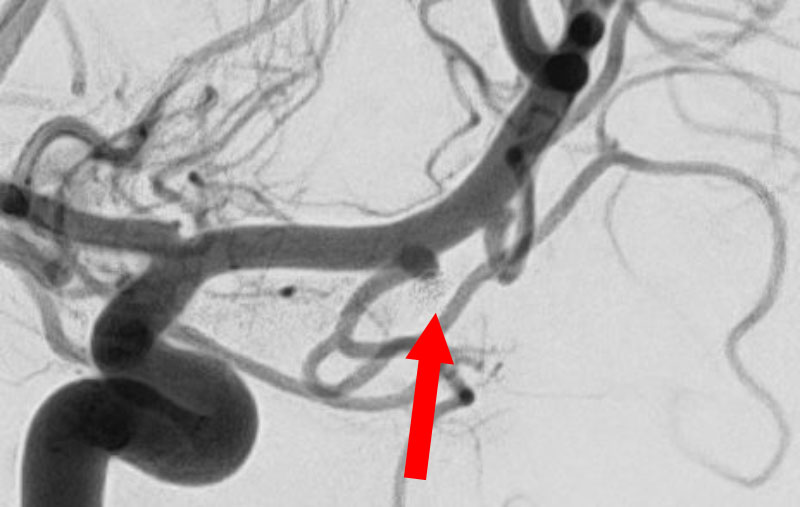

No.1627 手術前